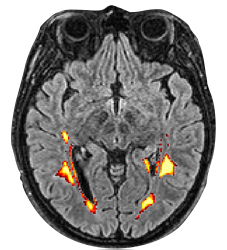

Probabilistic lesion volume map generated by LST-AI on a FLAIR image in axial view.

LST-AI – Deep Learning Ensemble for Accurate MS Lesion Segmentation – segments T2 hyperintense lesions in FLAIR images. LST-AI is an advanced deep learning-based extension of the original LST toolbox. LST-AI was trained using an ensemble network model with data from 491 Multiple Sclerosis patients with severe lesion patterns. It also labels lesions such as periventricular, infratentorial, juxtacortical, and subcortical according to the 2017 McDonald criteria. Further information on the algorithm can be found in the publication by Wiltgen, 2024.

The LST-AI pipeline implemented in neuGRID requires FLAIR and T13D images of the subject. Lesion volume values are corrected by dividing by the subject’s Total Intracranial Volume, calculated by SPM12, and multiplying by a constant.